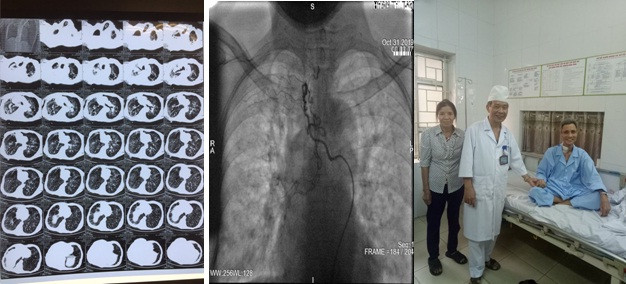

Các bác sĩ Trung tâm Nội Hô hấp, Bệnh viện Quân y 103 đã cấp cứu thành công một bệnh nhân nam 62 tuổi, ở Vĩnh Tường, Vĩnh Phúc, bị ho ra máu mức độ rất nặng.

Trước đó, bệnh nhân có tiền sử điều trị lao phổi 20 năm. Ba tháng gần đây bệnh nhân xuất hiện ho ra máu dai dẳng, ho máu tăng dần, mặc dù đã được điều trị nội khoa tích cực nhưng tình trạnh ho máu không thuyên giảm.

Bệnh nhân chuyển tới Trung tâm Nội Hô hấp, Bệnh viện Quân y 103 trong tình trạng thể trạng suy kiệt nặng (35kg/158cm), gù vẹo cột sống, 2 phổi bị xơ, giãn phế quản nặng.

Vào khoảng 22 giờ ngày 30/10/2019, bệnh nhân đột ngột ho máu số lượng khoảng 600ml màu đỏ tươi, biểu hiện suy hô hấp: tím tái, huyết áp tụt.

Các bác sĩ đã nhanh chóng khai thông đường thở, đặt ống nội khí quản, thở máy và ngay lập tức kích hoạt kíp trực can thiệp mạch cấp cứu. Sau 3 giờ can thiệp, bệnh nhân được chuyển về Trung tâm Hồi sức cấp cứu tiếp tục theo dõi. 2 ngày sau bệnh nhân được rút ống nội khí quản, ý thức và vận động hoàn toàn bình thường, bệnh nhân chỉ khạc ít đờm lẫn máu cũ.

Phó giáo sư, Tiến sĩ Mai Xuân Khẩn - Phó giám đốc Trung tâm Nội Hô hấp, người đã trực tiếp tham gia và chỉ đạo kíp cấp cứu nhận định, có thể nói đây là kỳ tích trong thực hành lâm sàng bởi lẽ bệnh nhân ho ra máu rất nặng tỷ lệ tử vong gần như 100% dù được cấp cứu kịp thời do tình trạng tắc nghẽn đường thở cấp tính nên được y văn gọi là "ho ra máu sét đánh".